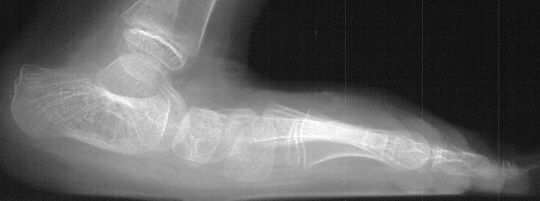

The

goal of this girl's surgery should be ambulating with plantigrade

feet in neutral varus/valgus angulation, normal knee extension

in stance phase, and no need for orthotics.